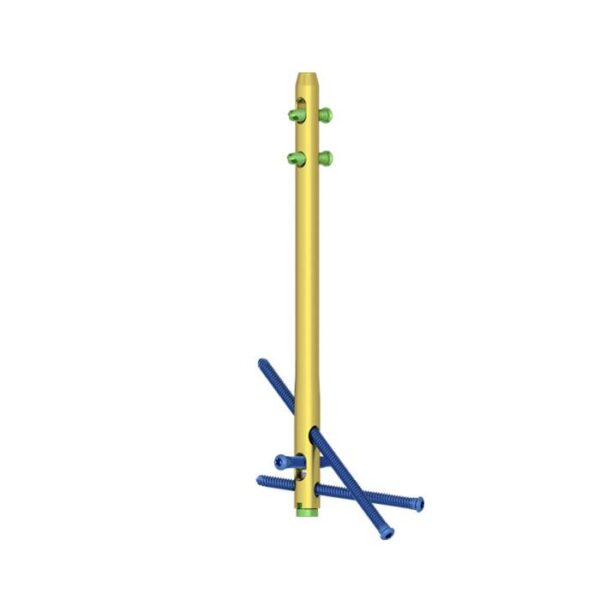

Clavo de artrodesis de tobillo:

- Proporcione diferentes diámetros y longitudes para más opciones clínicas.

- Los diferentes colores son fáciles de distinguir.

Orificios de bloqueo estáticos y dinámicos:

- Proporcione orificios de bloqueo estáticos y dinámicos en el proximal.

Tornillos distales para cepillado múltiple que cruzan los orificios de bloqueo:

- Fijación de articulaciones cruzadas para mejorar la estabilidad de la fusión.

- El tornillo se inserta oblicuamente en la apófisis anterior del calcáneo o en la articulación calcáneo-cuboidea para mejorar la fuerza y la estabilidad de extracción.

Tornillos de bloqueo:

- Diseño de ranura autorroscante para facilitar la inserción.

- Rebajo Torxdrive del diseño de la cabeza del tornillo para reducir el tornillo suelto.

- Agujeros proximales dinámicos y estáticos con tornillo de bloqueo de 5.0 mm.

- Tres orificios transversales distales coinciden con el tornillo de bloqueo de 6,0 mm.

Tapa final:

- Evita que los tejidos blandos crezcan.